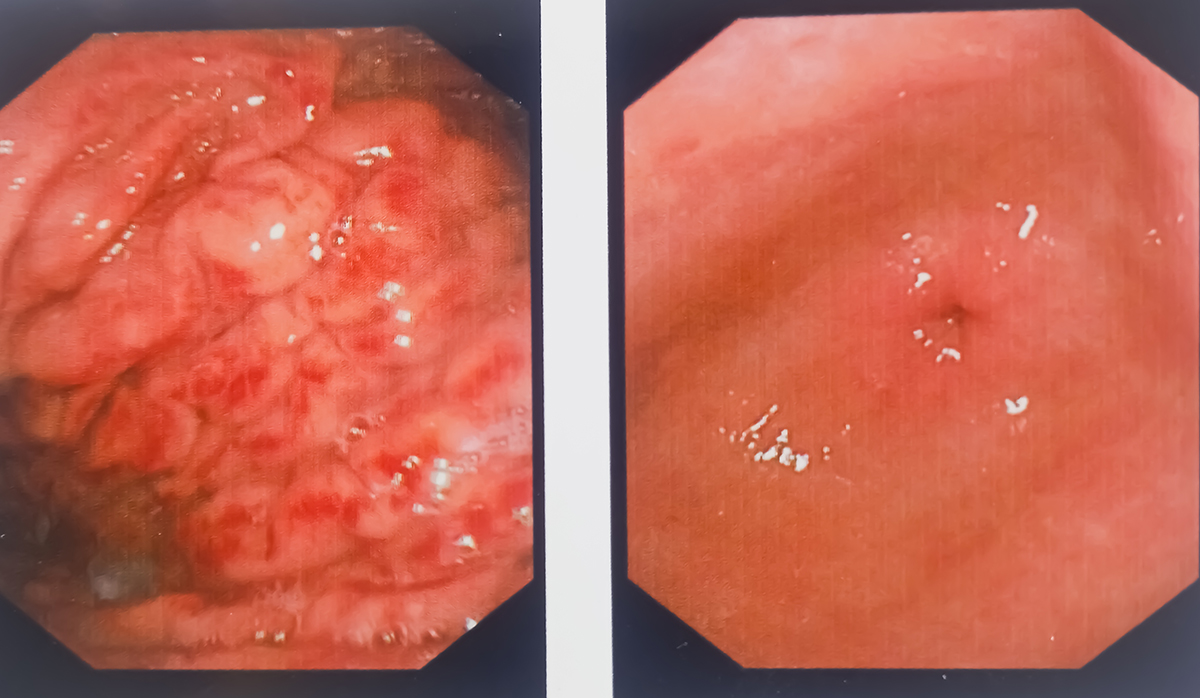

Hiatus hernia with severe gastritis. Gastrointestinal endoscopy, medical imaging EGD looking for structures in the esophagus.